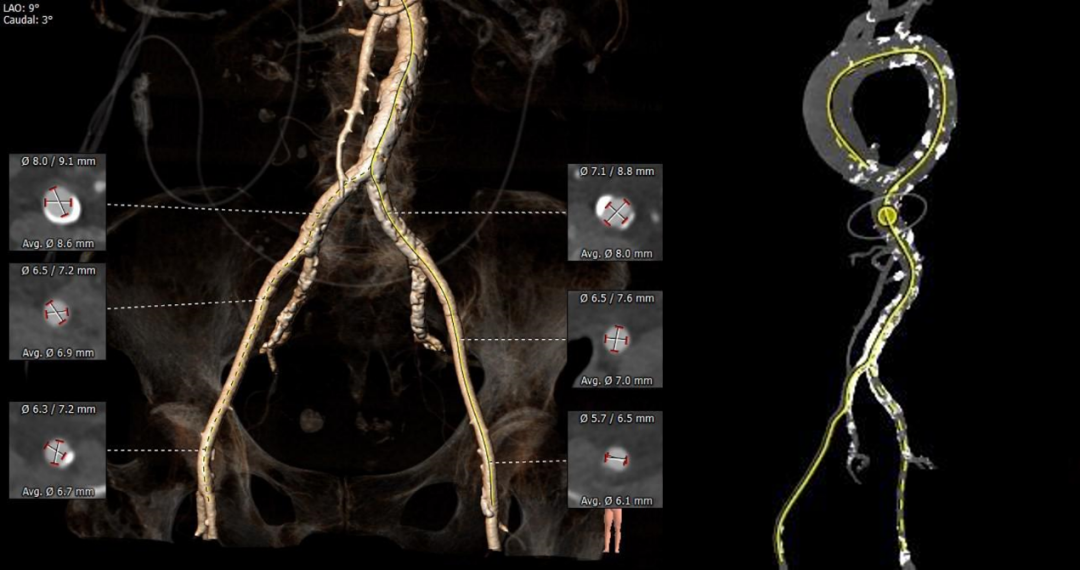

弓部及入路评估

入路血管散在斑片状钙化,髂动脉分叉前后较严重,局部合并较严重粥样硬化改变,双侧血管内径良好,整体入路血管条件尚可。